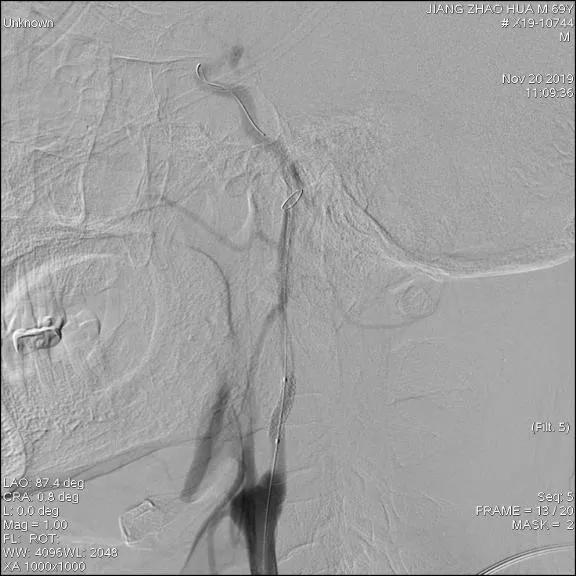

全脑血管造影图

造影图提示:支架位置佳,膨胀好,未见内漏,原狭窄段基本恢复正常。

手术顺利,术中患者生命体征平稳,术毕拔管包扎,安返病房。